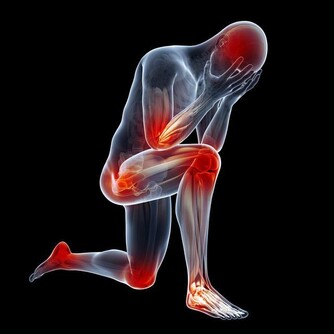

世界衛生組織早已將“久坐”列為十大致死致病元兇之一。

特別是中老年人血脂高,血液粘稠度高,久坐是潛在的可怕危險因素。